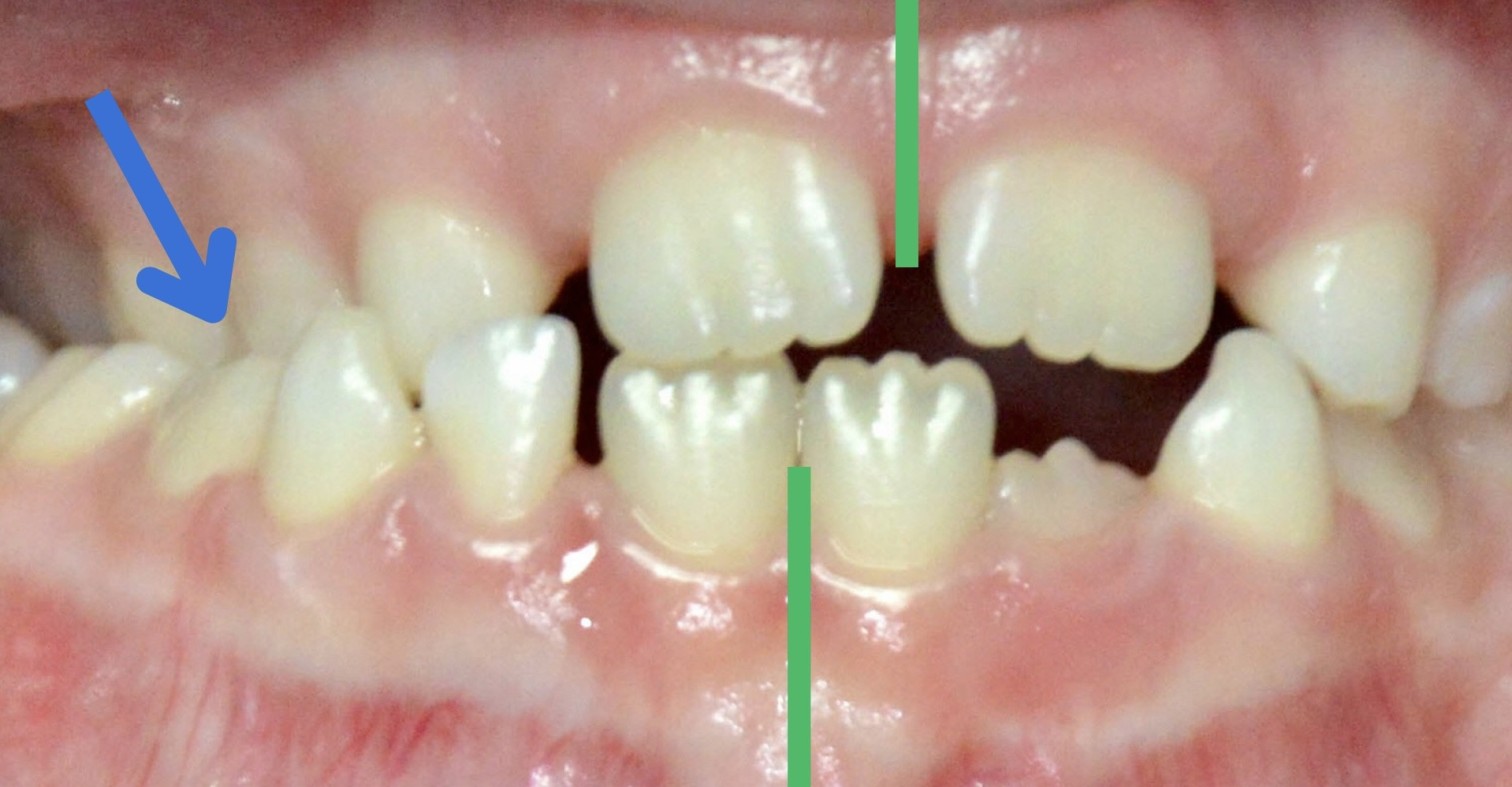

Jetzt stellen wir uns einmal vor, wir schauen in eine Mund und es sieht so aus wie auf Bild 2: Hier stimmt doch etwas nicht. Bei der genaueren Betrachtung fällt auf, dass der Oberkiefer auf der rechten Seite des Patienten zu schmal ist und nicht über den Unterkiefer beißen kann.

Dadurch stehen die unteren Zähne auf der Seite weiter außen als die oberen. Der Unterkiefer ist zu einer Seite verschoben. Diesen Biss nennen wir Kreuzbiss, da sich ab einem bestimmten Zahn – hier Eckzahn – die Seiten kreuzen. Zusätzlich ist die Mittellinie zur Seite des Kreuzbisses verschoben (grüne Striche).